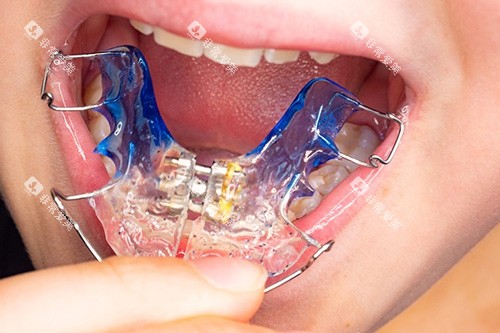

牙齿矫正:传统金属托槽5680元起(含普通保持器),自锁托槽12500元起(减复诊次数),隐适美隐形矫正28800元起(含5副精调牙套)。若需拔牙,正畸牙80-300元起/颗,智齿200-800元起/颗。

在梧州分院,5岁的朵朵正张着嘴让廖鑫医生检查牙齿。“我们采用MRC肌功能矫治器,”廖医生指着孩子嘴里的粉色牙套说,“2900元起就能预防地包天,比成年后再做正颌手术省十几万。”这种“早发现早干预”的理念,让蓝天口腔的儿童牙科占比达到35%。